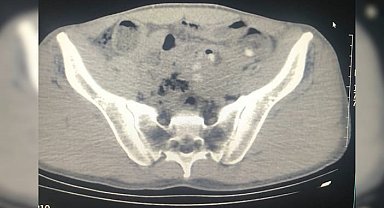

Midelerinde uyuşturucu ile yakalanan yabancı uyruklu 3 şüpheli tutuklandı